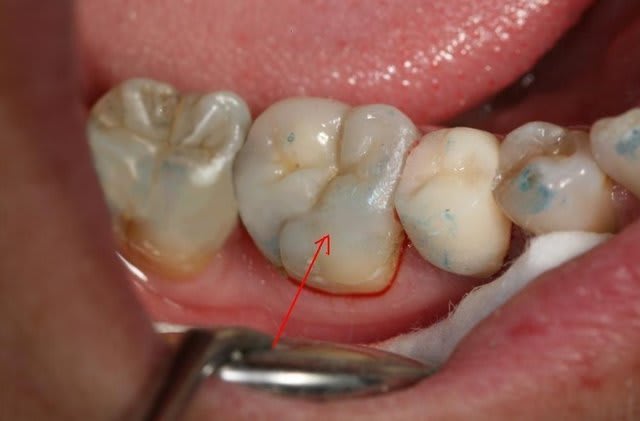

> Je ne comprends toujours pas pourquoi tu n'as pas

> refait le joint en compo fluide en vestibulaire

> avant prendre les photos qui montrent toujours la

> moche adaptation à cet endroit.

> En lingual, je n'ai rien à redire.

Par honneteté intellectuelle.. si si ca existe.

Je referrai le joint la prochaine fois c'est prévu mais je voulais avant cela vous montrer la restauration sous un autre angle

il vaut mieux un défaut de joint comme ici en occlusal qu'en proximal. A cet endroit, le brossage réussira à diminuer le risque d'infiltration.

Imaginons un défaut d'adptation comme çà en proximo-cervical, c'est impossible à voir.